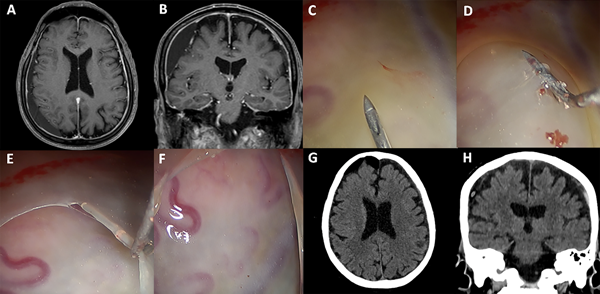

Caso ilustrativo: Paciente de 78 años con antecedente de hipertensión arterial, diabetes y una reciente resección endoscópica endonasal-transoral de tumor de cavum. Consulta por trastorno de la marcha posterior a un traumatismo craneoencefálico. Examen físico con paresia 3/5 braquiocrural izquierda. Con tomografía computada se diagnosticó HSDC. Por el antecedente quirúrgico reciente de tumor de cavum se decidió evitar la intubación orotraqueal. Se realizó sedación consciente con dexmedetomedina y bloqueo de scalp. Se procedió a la evacuación endoscópica de HSDC por 2 trépanos. El paciente tuvo una buena evolución clínica-radiológica. Se otorgó el alta a las 48 horas (Figura 4).

Figura 4: Caso ilustrativo. A-B: Resonancia magnética preoperatoria. C-F: Apertura endoscopia de la membrana visceral. G-H: Tomografía postoperatoria.